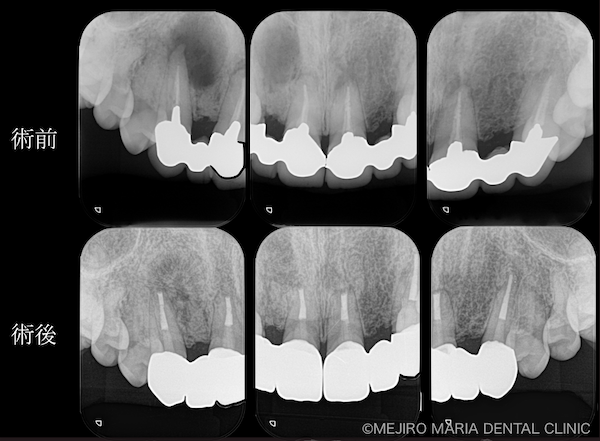

【再根管治療(感染根管治療)】

感染した歯髄や腐敗物、細菌を取り除く治療

再根管治療とは、過去に行った根管治療のやり直しを行う処置です。根尖性歯周炎の原因は根管内に潜む細菌感染ですので、根管内の細菌数を無菌的環境下で減少させ、密に封鎖することで予知性を高めることが可能です。